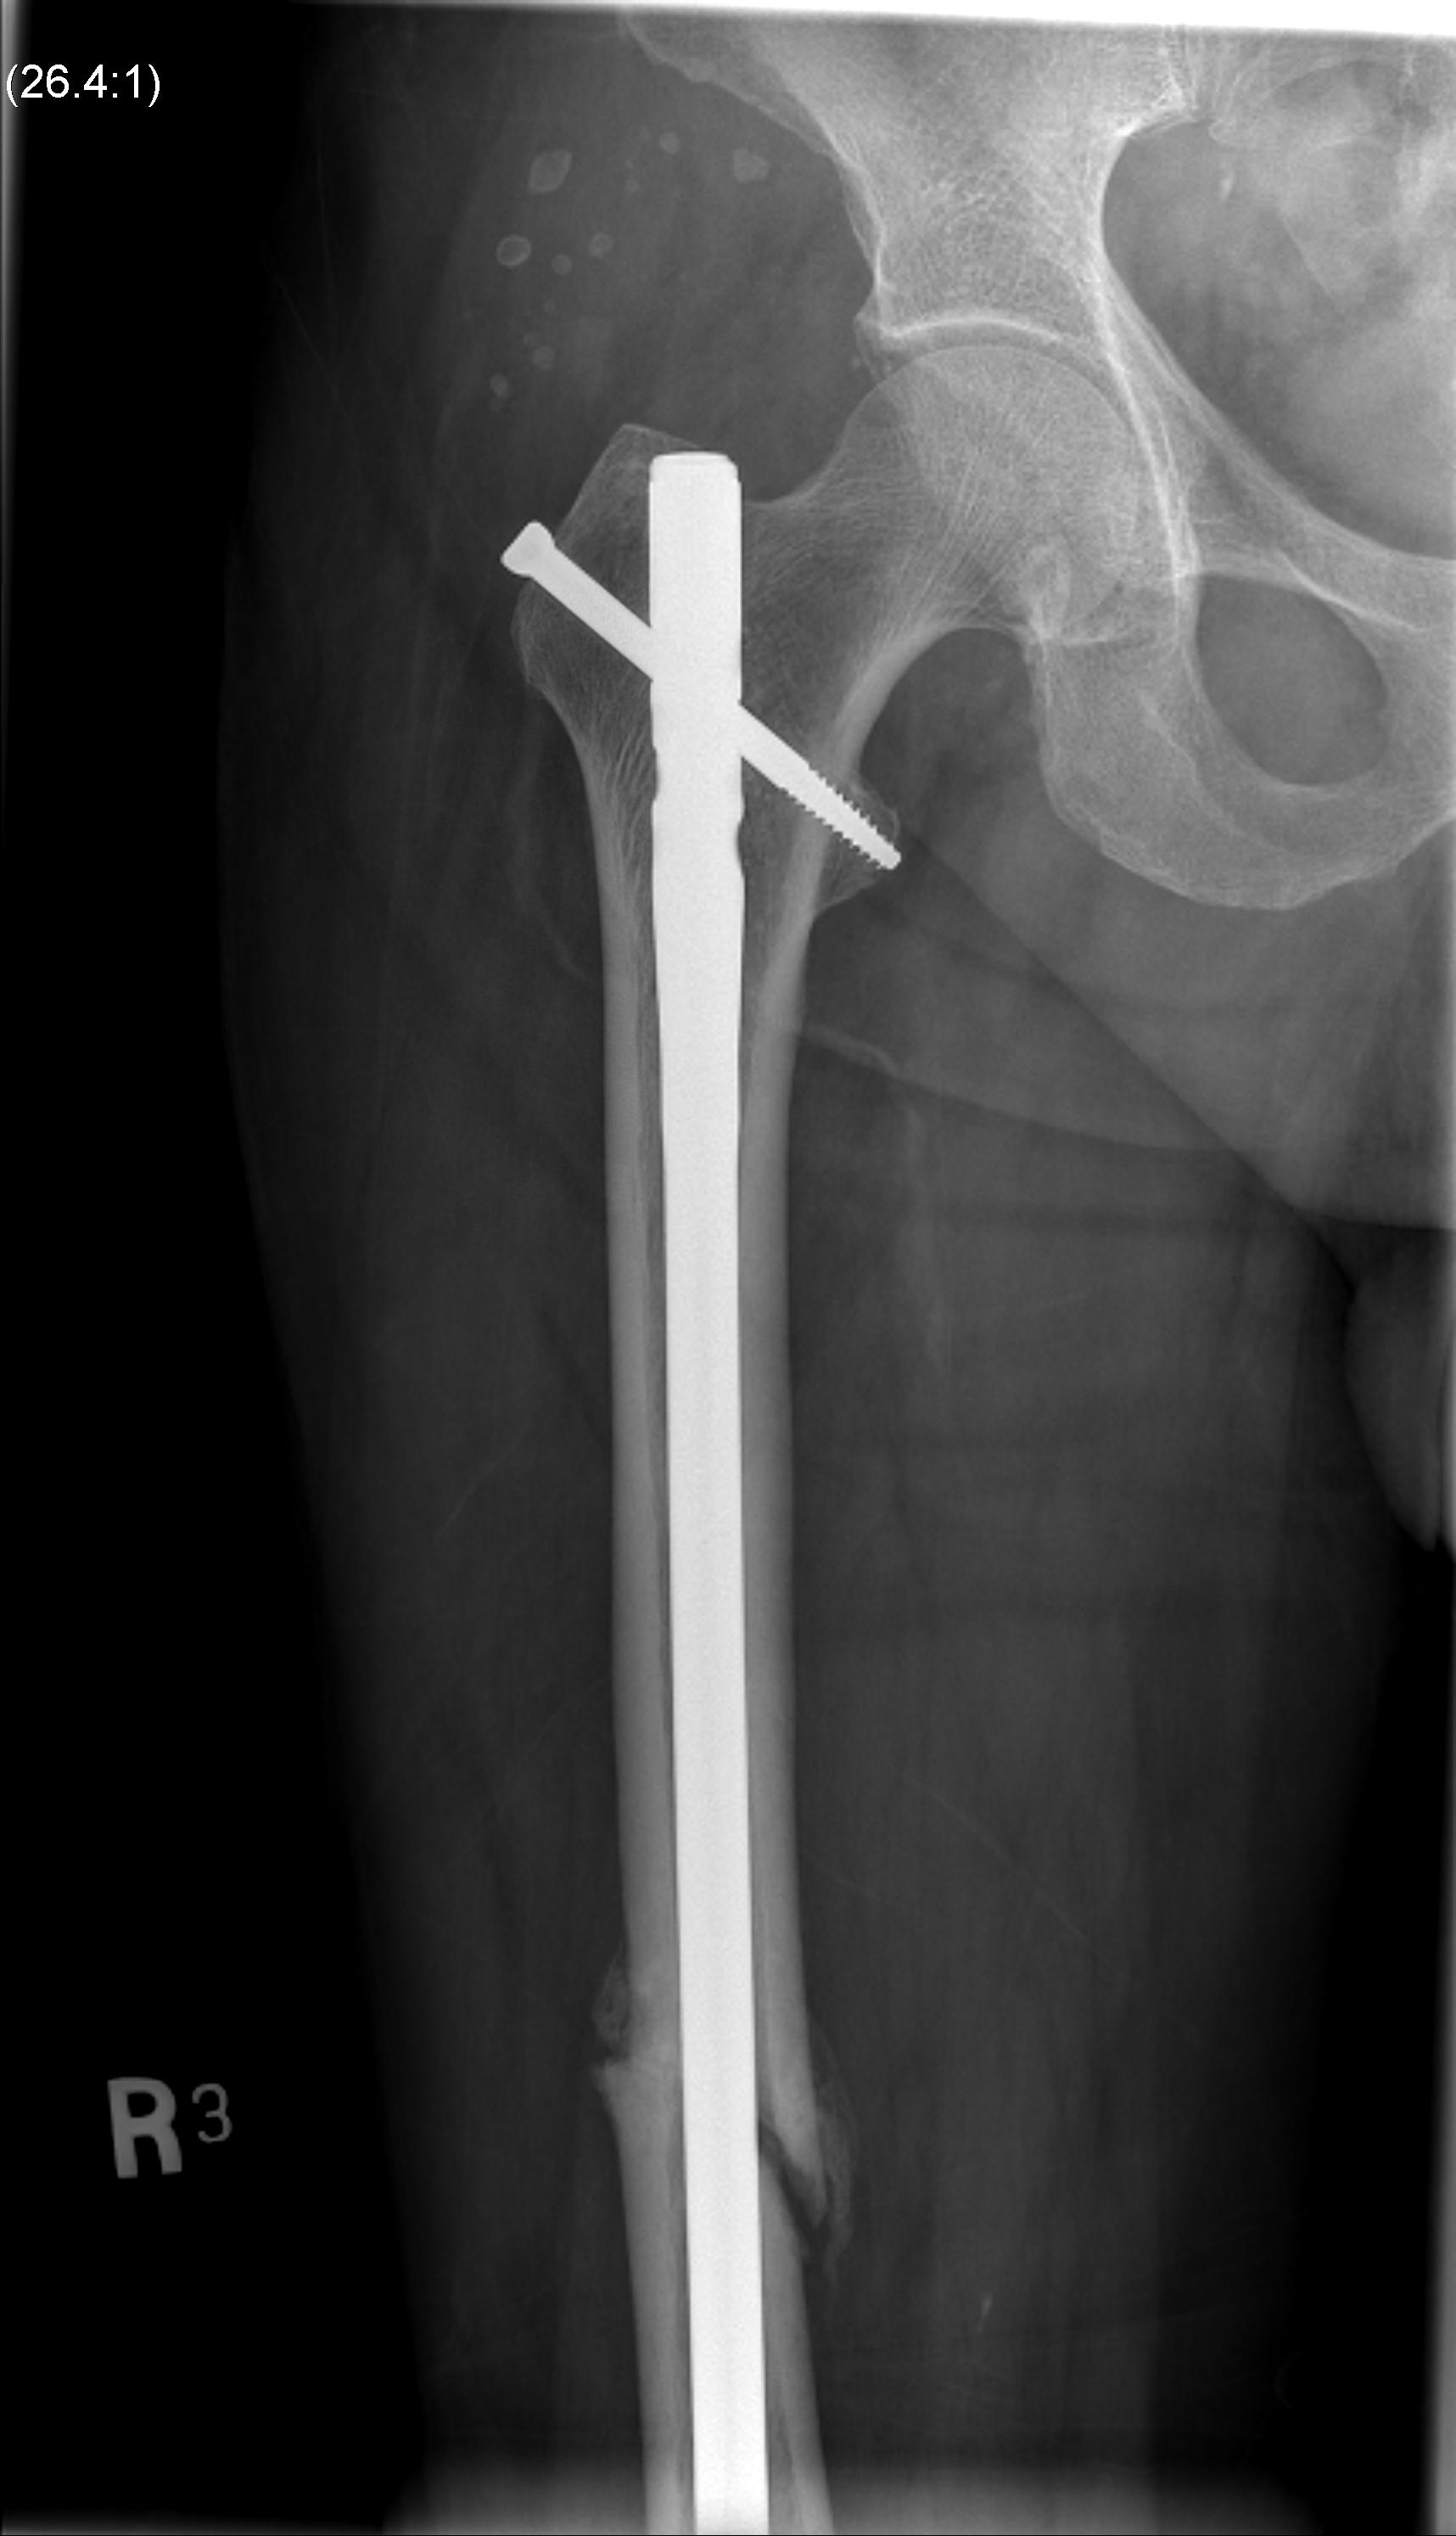

Intramedullary Nails

Indication

- for fixation of the diaphysis of long bones

- reamed vs unreamed

- initial nails relied on interference fit on either side of the fracture and hence could only be successfully applied to midshaft fractures

- interlocked nails have expanded indications to distal and proximal 1/3 shaft fractures